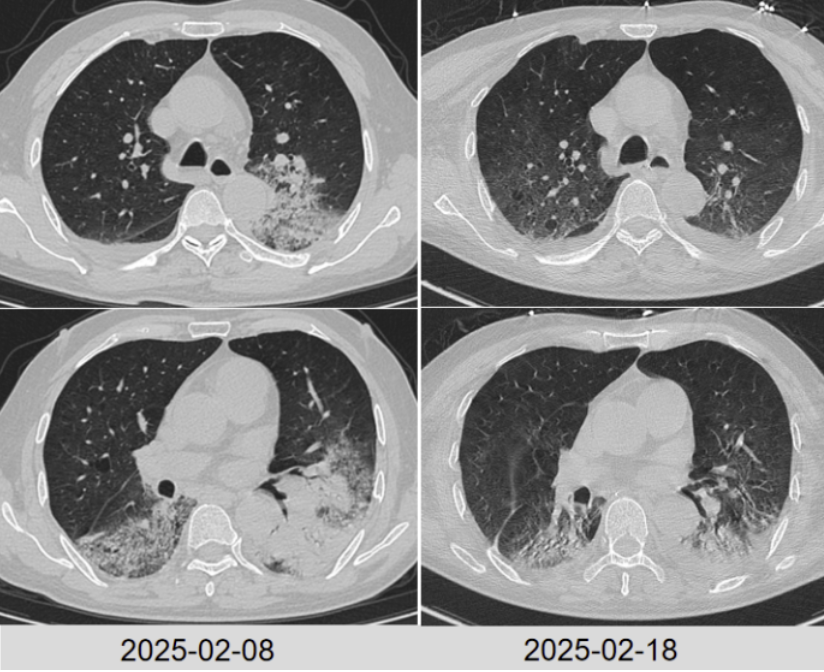

2025年4月14日发热,体温最高40℃,感染指标升高,伴氧合下降。

2025年4月16日复查胸部CT明显进展(图7)。调整头孢哌酮舒巴坦为美罗培南+莫西沙星抗感染,无创呼吸机辅助通气,入重症康复科ICU。

图7 患者胸部CT较前变化